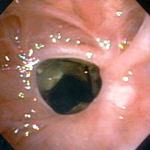

Стеноз дыхательных путей на фоне гранулематоза с полиангиитом (ранее именуемого гранулематозом Вегенера)

Из коллекций Хосе Фернандо Сантакруза, дипломированного врача, члена Американской коллегии специалистов в области торакальной медицины, DAABIP, и Эрика Фолка, дипломированного врача, магистра наук; используется с разрешения